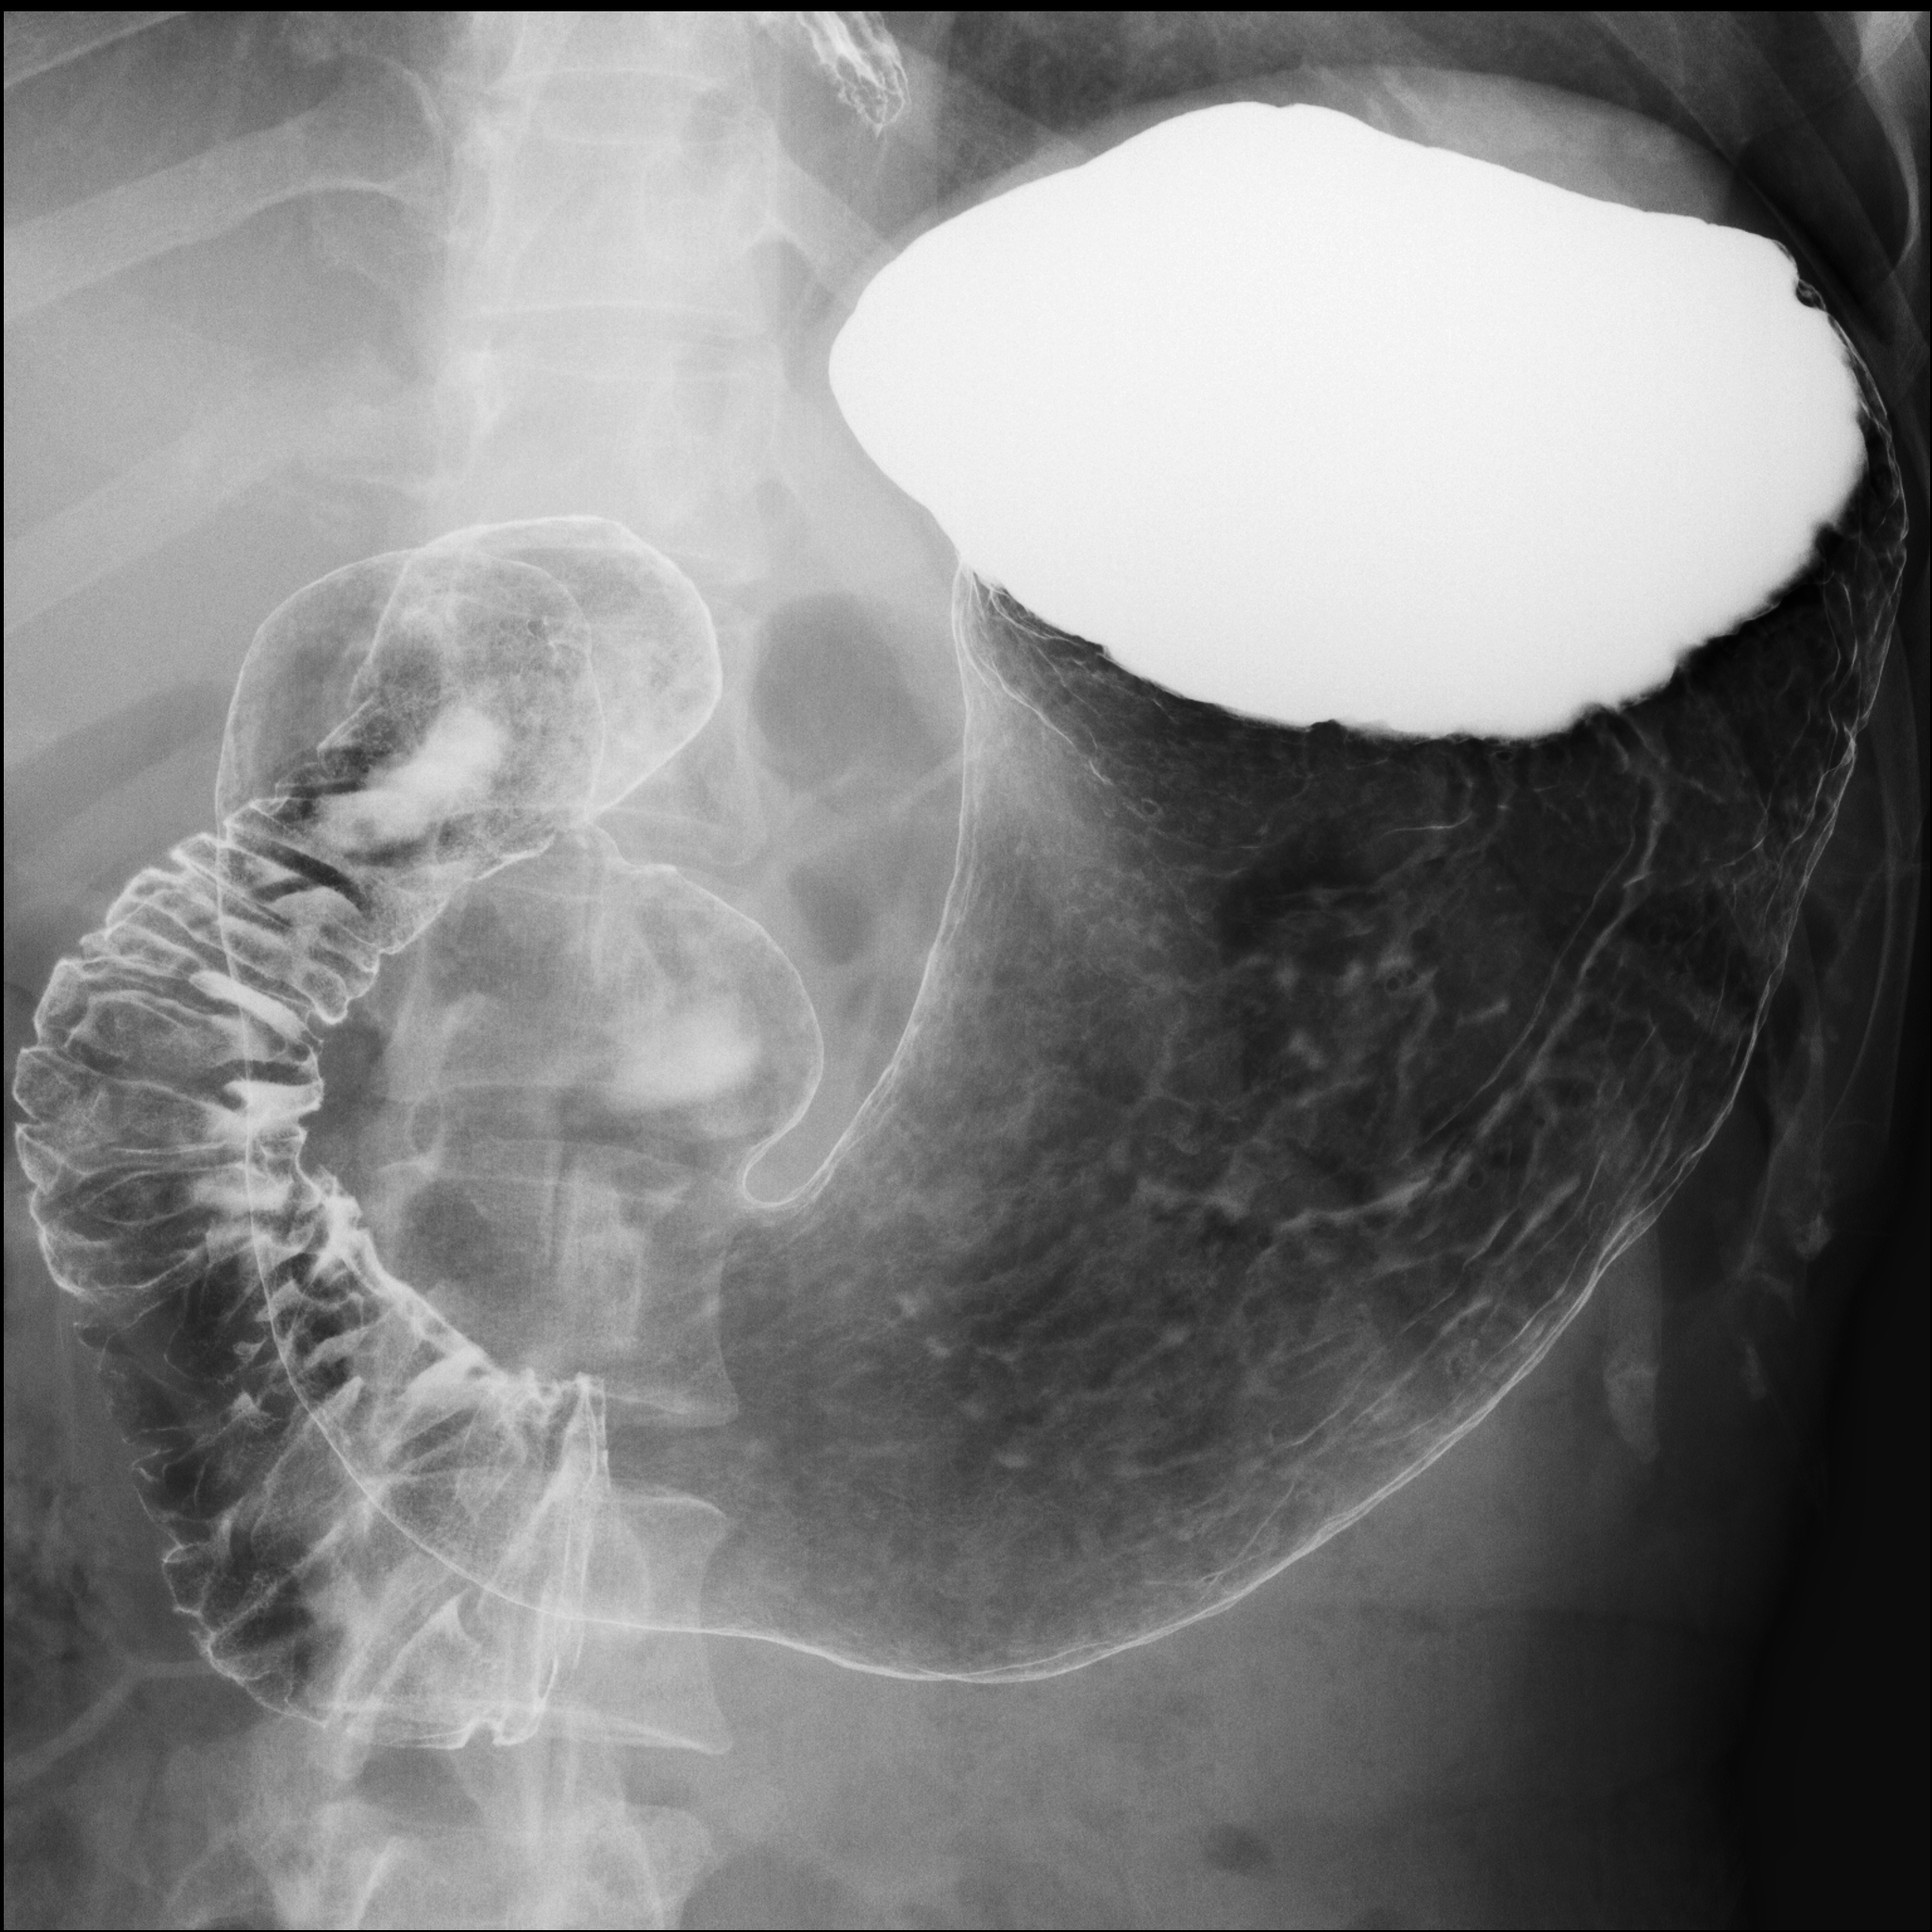

Figures 1 and 2 show the full gastric X-ray images and patch-based gastric X-ray images, respectively.

This subsection shows the experimental settings of our research. The dataset used in our study contains 815 patients' (240 gastritis and 575 non-gastritis) gastric X-ray images. Each image has a ground truth (gastritis/non-gastritis), which was determined by patient diagnosis results of endoscopic examination and X-ray inspection. All of the gastric X-ray images are gray-scale and high-resolution. The training dataset contains 200 patients' (100 gastritis and 100 non-gastritis) images. Also, the rest of the patients' (140 gastritis and 475 non-gastritis) images are included in the test dataset. In the data preprocessing stage, we divided the images into patches (299 299 pixels), , = = 35, where the sliding interval was set to 50 pixels. Besides, the patches extracted from the training dataset were labeled as , and by a radiological technologist. Note that if the regions inside of the stomach were less than 1 in a patch, it was labeled as . In addition, if the regions inside of the stomach were more than 85 in a patch, it was labeled as or . And we discarded the rest of the patches in the training dataset. As a result, we obtained , and whose number of patches were 48,385, 42,785 and 45,127, respectively.